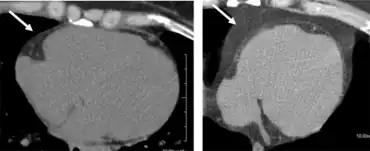

![]() | |

| A man with marked central obesity, a hallmark of metabolic syndrome. His weight is 182 kg (400 lbs), height 185 cm (6 ft 1 in), and body mass index (BMI) 53 (normal 18.5 to 25). | |